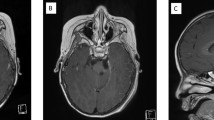

The patient was a 4-year-and 3-month-old boy who experienced status epilepticus at the age of 1 year and 8 months, leading to an emergency visit to a local doctor. Head magnetic resonance imaging (MRI) revealed extensive cortical dysplasia in the right cerebral hemisphere, and focal epilepsy treatment was initiated (Fig. 1A–B). The seizures persisted despite trying various antiseizure medications, and developmental regression occurred. Subsequently, the patient was referred to our department for surgical intervention. Physical examination revealed a manual muscle testing grade 2, with left-sided hemiparesis, especially in the left hand, and restricted isolated movement of an unknown degree. Seizure semiology included daily convulsions on the left side of his body with left conjugate deviation of the eyes. EEG revealed a right frontal predominant spike and wave complex (Fig. 1C). We suspected an extensive epileptogenic zone in the right cerebral hemisphere and opted for hemispherotomy. Detailed methods of intraoperative MEP are presented in Supplementary information.

A, B Preoperative cranial T2-weighted magnetic resonance imaging, axial section, revealing wide cortical dysplasia in the right cerebral hemisphere. C Preoperative interictal EEG indicating frequent bilateral synchronous spike and wave activity in the right frontal region. Sampling rate of 500 Hz, high-frequency filter of 60 Hz, and time constant of 0.3 s. D, E Postoperative cranial T2-weighted magnetic resonance imaging, axial and coronal sections, respectively, depicting complete detachment of the right thalamus from the right hemisphere. F Postoperative interictal EEG with lateralized interictal epileptiform discharges in the right hemisphere. Sampling rate of 500 Hz, high-frequency filter of 60 Hz, and time constant of 0.3 s

Surgery was completed without any complications. Postoperative MRI and EEG confirmed the anatomical and electrophysiological success of the hemispherotomy (Fig. 1D–F). Postoperatively, the degree of paralysis in the left upper and lower extremities remained unchanged, and the seizures disappeared.